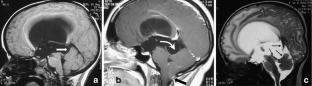

The sylvian aqueduct is the most common site of intraventricular blockage of the cerebro-spinal fluid. Clinical aspects, neuroradiological appearance, and treatment of hydrocephalus secondary to aqueductal stenosis are specific.

The correct interpretation of the modern neuroradiologic techniques may help in selecting adequate treatment between the two main options (third ventriculostomy or shunting). In the last decades, endoscopic third ventriculostomy has become the first-line treatment of aqueductal stenosis; however, some issues, such as the cause of failures in well selected patients, long-term outcome in infant treated with ETV, and effect of persistent ventriculomegaly on neuropsychological developmental, remain unanswered.